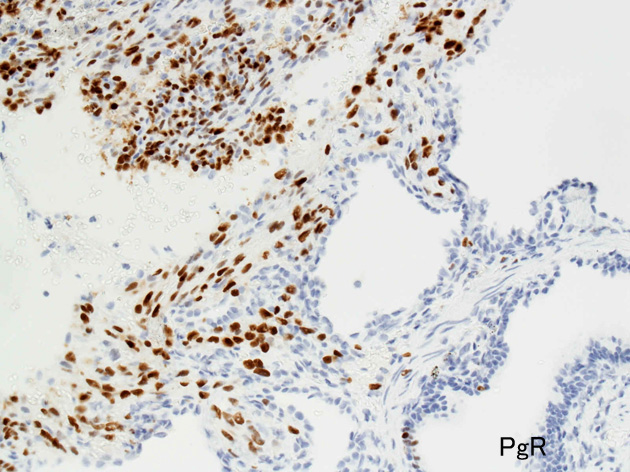

免疫染色

PgR.jpg

Estrogen receptorProgesteron receptor